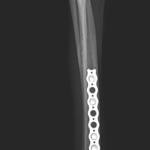

橈骨固定術 #239

イタリアングレーハウンドがジャンプした後から跛行しているとの事。2.4 Locking Plateで固定術を行いました。しばらくはインプラントにロードベアリングしているため骨がロードシェアできるまでは初期固定強度を担保するために外固定の併用を行います。